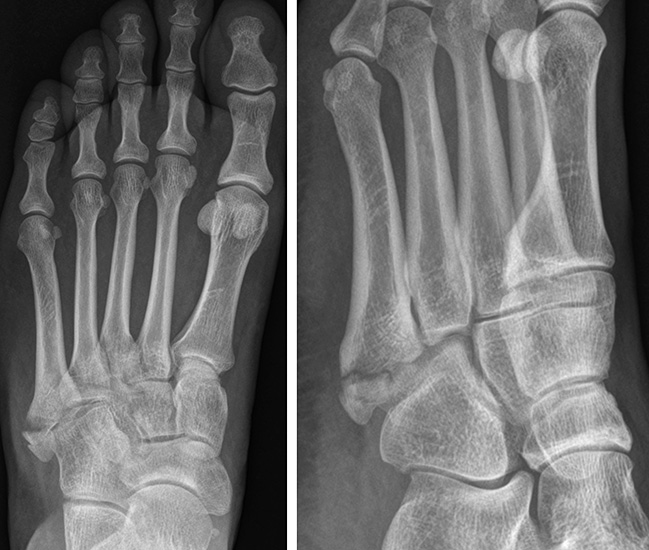

Sir Robert Jones erlitt beim Tanzen eine Fraktur seines 5. Mittelfußknochens, „three-fourths of an inch [1.9 cm] from its base“. 1902 publiziert er eine erste Fallserie mit seinem Fall und fünf weitere Patienten mit einer MT V Basisfraktur. Seitdem wurden verschiedene Frakturlokalisation im Bereich der MT V Basis als Jones Frakturen bezeichnet, was den Begriff sehr unscharf gemacht hat. Insgesamt sind in der Literatur mehr als 20 verschiedene Klassifikationen der MT V Basisfraktur beschrieben. Im Folgenden sollen die beiden am häufigst angewandten vorgestellt werden. Die Frakturklassifikation erfolgt anhand der schrägen Röntgenaufnahme.

Die in der Literatur am häufigsten verwendete Klassifikation ist die 1993 publizierte, anatomische Klassifikation von Lawrence und Botte 6. Diese basiert auf einer retrospektiven Fallserie und unterscheidet drei Frakturzonen (Abb. 1).

Zone II befindet sich auf Höhe der Articulatio zwischen MT IV und V. Die Zone I liegt proximal, die Zone III distal davon. Interessanterweise vermischen Lawrence und Botte Unfallmechanismen (Avulsionsfraktur/Stressfraktur) und deskriptive Terminologie (Jones’ Fraktur) in ihrer Klassifikation. Eine Vereinfachung dieser Klassifikation publizierten Polzer et al. 2012 7. Basierend auf den Ergebnissen von sechs prospektiven Behandlungsstudien (systematische Literaturrecherche), schlussfolgerten die Autoren, dass Lawrence und Botte Zone I und II Frakturen zusammengefasst werden könnten (Metaphysäre Frakturen). Zone III Frakturen werden als Meta-Diaphysär beschrieben.